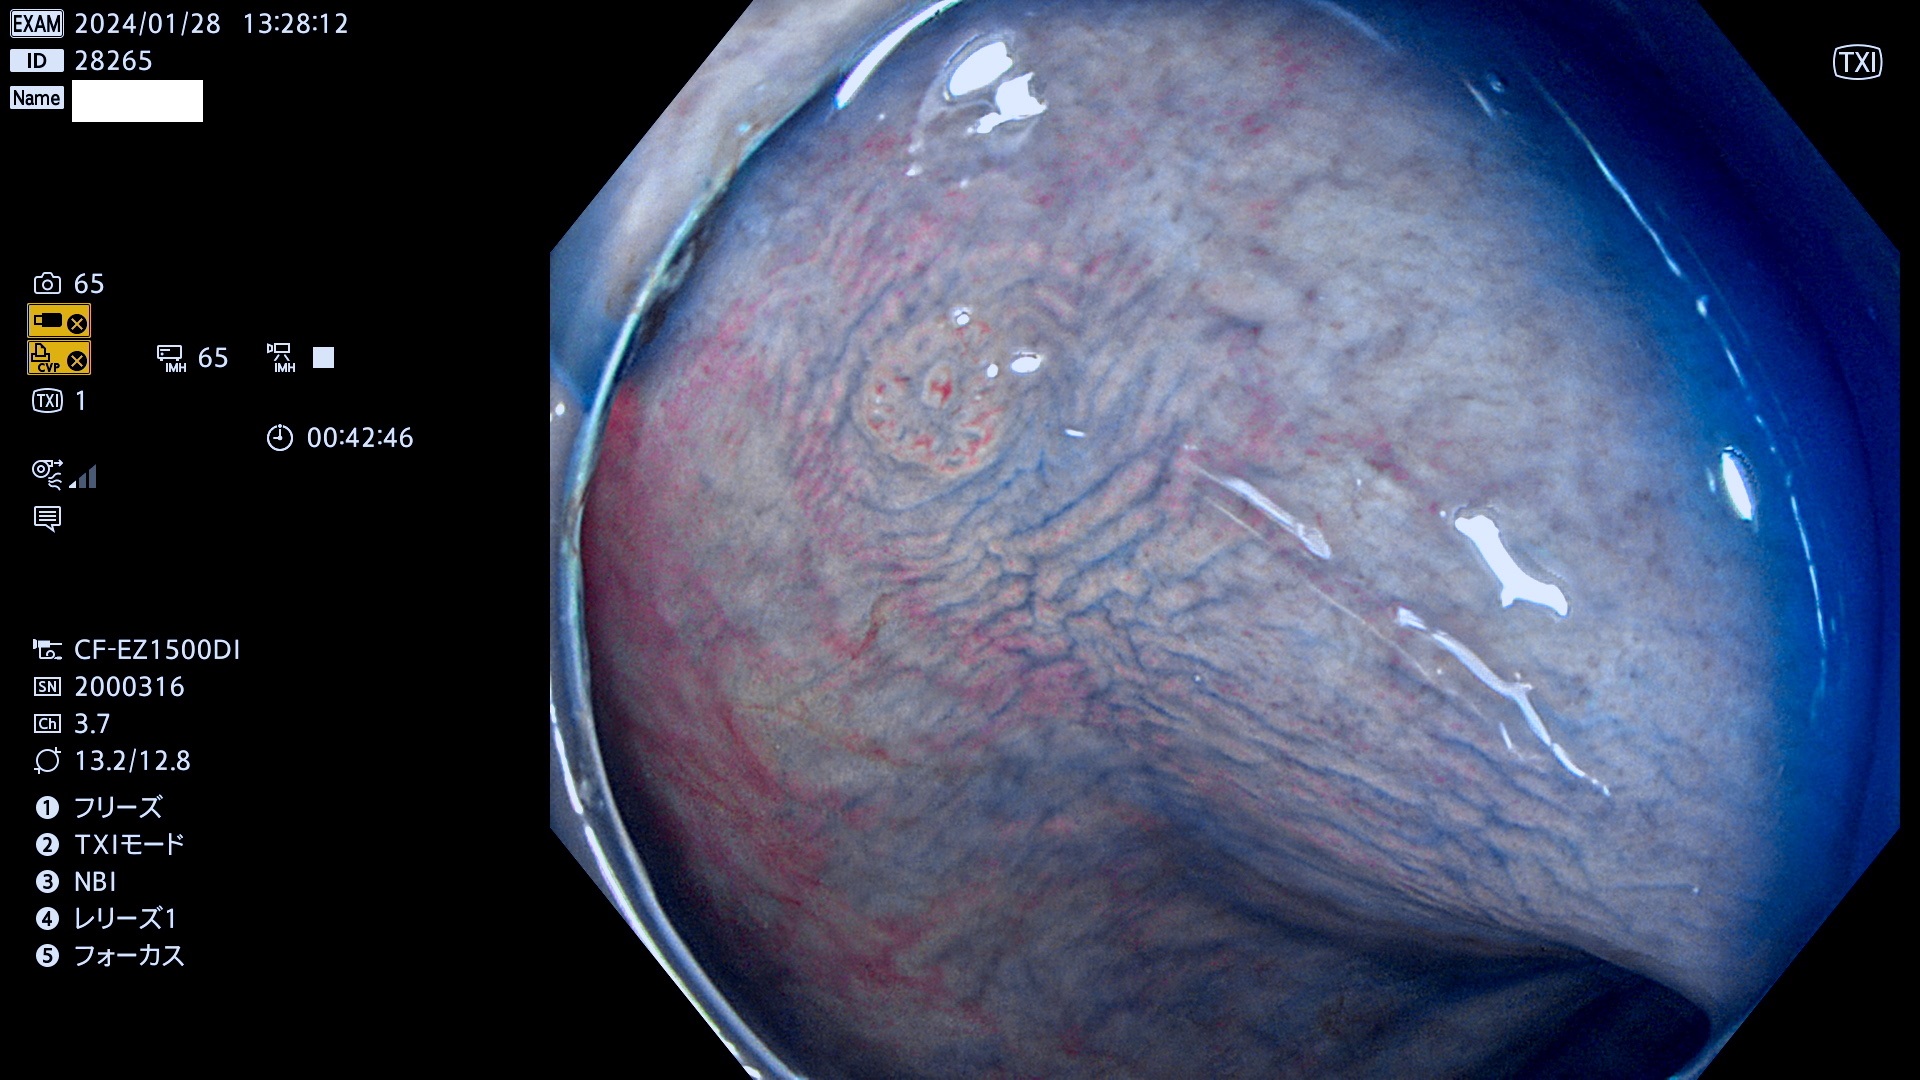

表面型腺腫(Flat Adenoma)の中で、完全に平坦な物をUb、陥凹している物をUcと呼びます。平坦隆起型(Ua)よりも、発見が難しく危険な病変です。

専門的)何故、陥凹していると危険? 癌遺伝子の変異が蓄積すると細胞分裂が盛んになり隆起するのでは?と通常は思われるでしょう。しかし実際は逆です。これは2022年の記事にある「細胞はストレスに直面したら細胞分裂を止める(細胞老化に入り休眠する)という生命の基本的現象」によるものです(Oncogene Stress)。細胞老化を起こすのが癌抑制遺伝子で、この安全装置(ブレーキ)が壊れると癌になります(休眠からの覚醒)。ですから陥凹は「まだ癌では無いが癌化の直前」を意味します。特に「小サイズなのに陥凹している」病変は短期間に腫瘍進化(⇒2021年記事)が起きたことを意味します(=ゲノム不安定性

毎週の検査(木・金・土・日)に発見されたUb、Uc型・腺腫を、その週の日曜の夜にUPし1週間、提示します。

抽出の対象期間 2024年1月25日(木)〜1月28(日)の4日間(40件の検査)9件